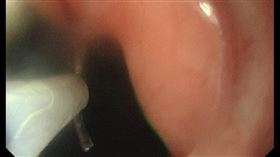

吃藥沒用!60歲男「喉嚨腫脹」檢查竟罹癌

期天氣變化大,許多民眾感冒、喉嚨痛。日前有名60多歲...